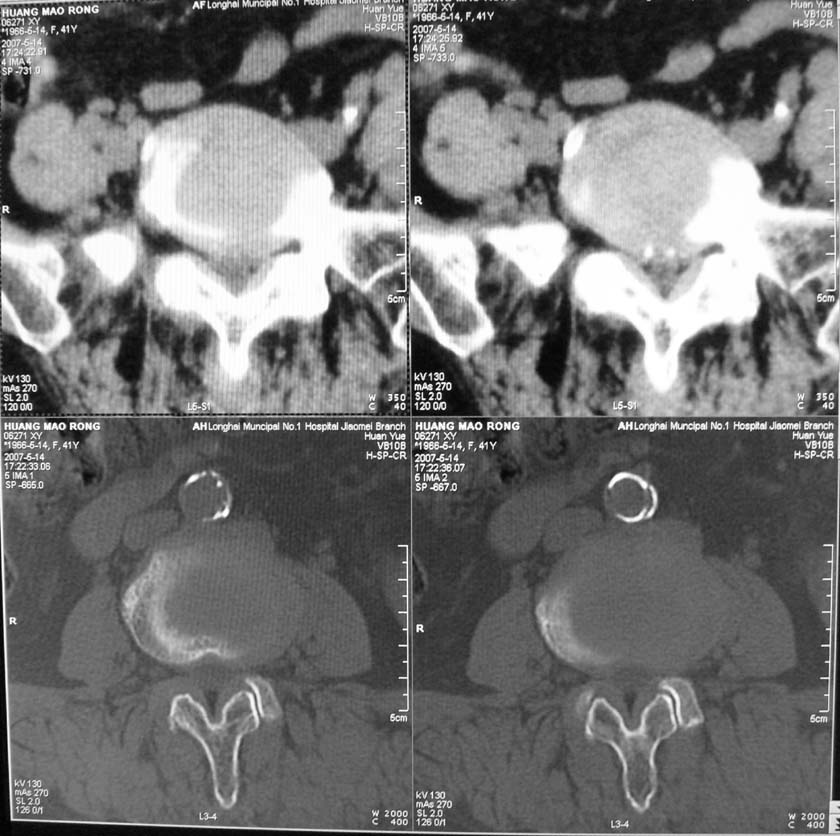

以下是引用jiangjing在2007-5-16 11:05:00的发言:[br]zhichi [br]ct所见:[br]l4-5椎间盘膨出,双侧黄韧带增厚,致使对应椎管变窄,硬膜囊受压.[br][br]l5-s1椎间盘后突,其后硬膜囊受压.l3-4椎间盘未见突出征象.[br]诸椎体边缘及对应椎小关节突骨质增生.腰椎生理曲度正常.[br]腹主动脉壁广泛钙化.[br]印象:[br]1、l4-5椎间盘膨出并双侧黄韧带肥厚及椎管狭窄。[br]2、l5-s1椎间盘突出。[br]3、腰椎及椎小关节退变。